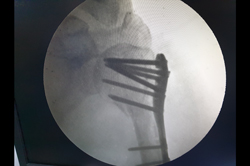

Intertrochanteric Fracture